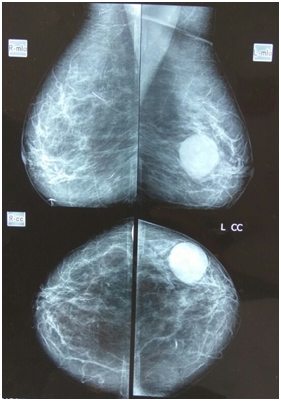

A forty years female presented with history of lump in left breast for last 9months. The lump was painless initially but for last 3months, this patient started having discomfort in the breast. The discomfort was not related to menstrual cycle. On examination there was 10x10cm lump in the left breast having smooth surface and non tender to touch. The consistency was firm and this left breast lump was freely mobile. On clinical examination this left breast lump appeared to be benign solid tumor. The mammography was done in this patient and diagnosis of benign mammary swelling was given (Figure 1). The ultrasound of the breast revealed a large size 10x10cm cystic swelling. This cystic swelling did not contain any solid tissue in it and surrounding tissue was normal. The diagnosis of giant simple mammary cyst was given.

Figure 1 Mammogram showing Giant Breast Cyst.